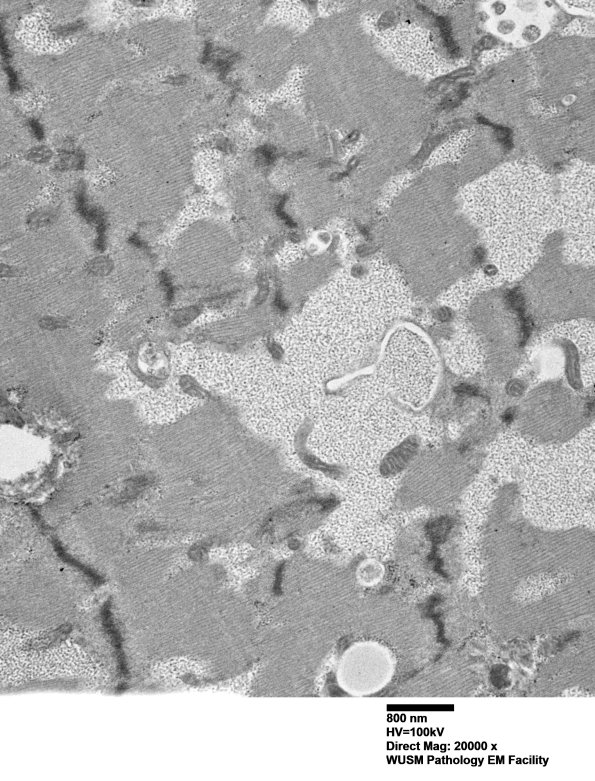

Washington University Experience | METABOLIC | Pompe Disease | 5D3 Muscle (Case 5) EM002 - Copy

Much of the granular material with the appearance of glycogen percolates between the sarcomeres and is not membrane bound. (electron micrograph)